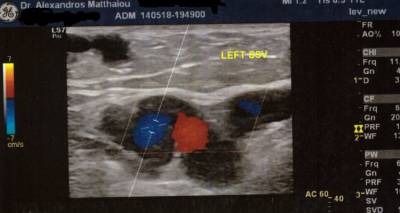

Ως το «πιο σημαντικό κομμάτι της φλεβολογίας» χαρακτηρίζει ο Αγγειοχειρουργός Αλέξανδρος Ματθαίου την υπερηχογραφική εξέταση του φλεβικού συστήματος, που πραγματοποιείται για χαρτογράφησή του, για διερεύνηση της λειτουργίας των βαλβίδων των φλεβών και τη διάγνωση των θρομβώσεων.